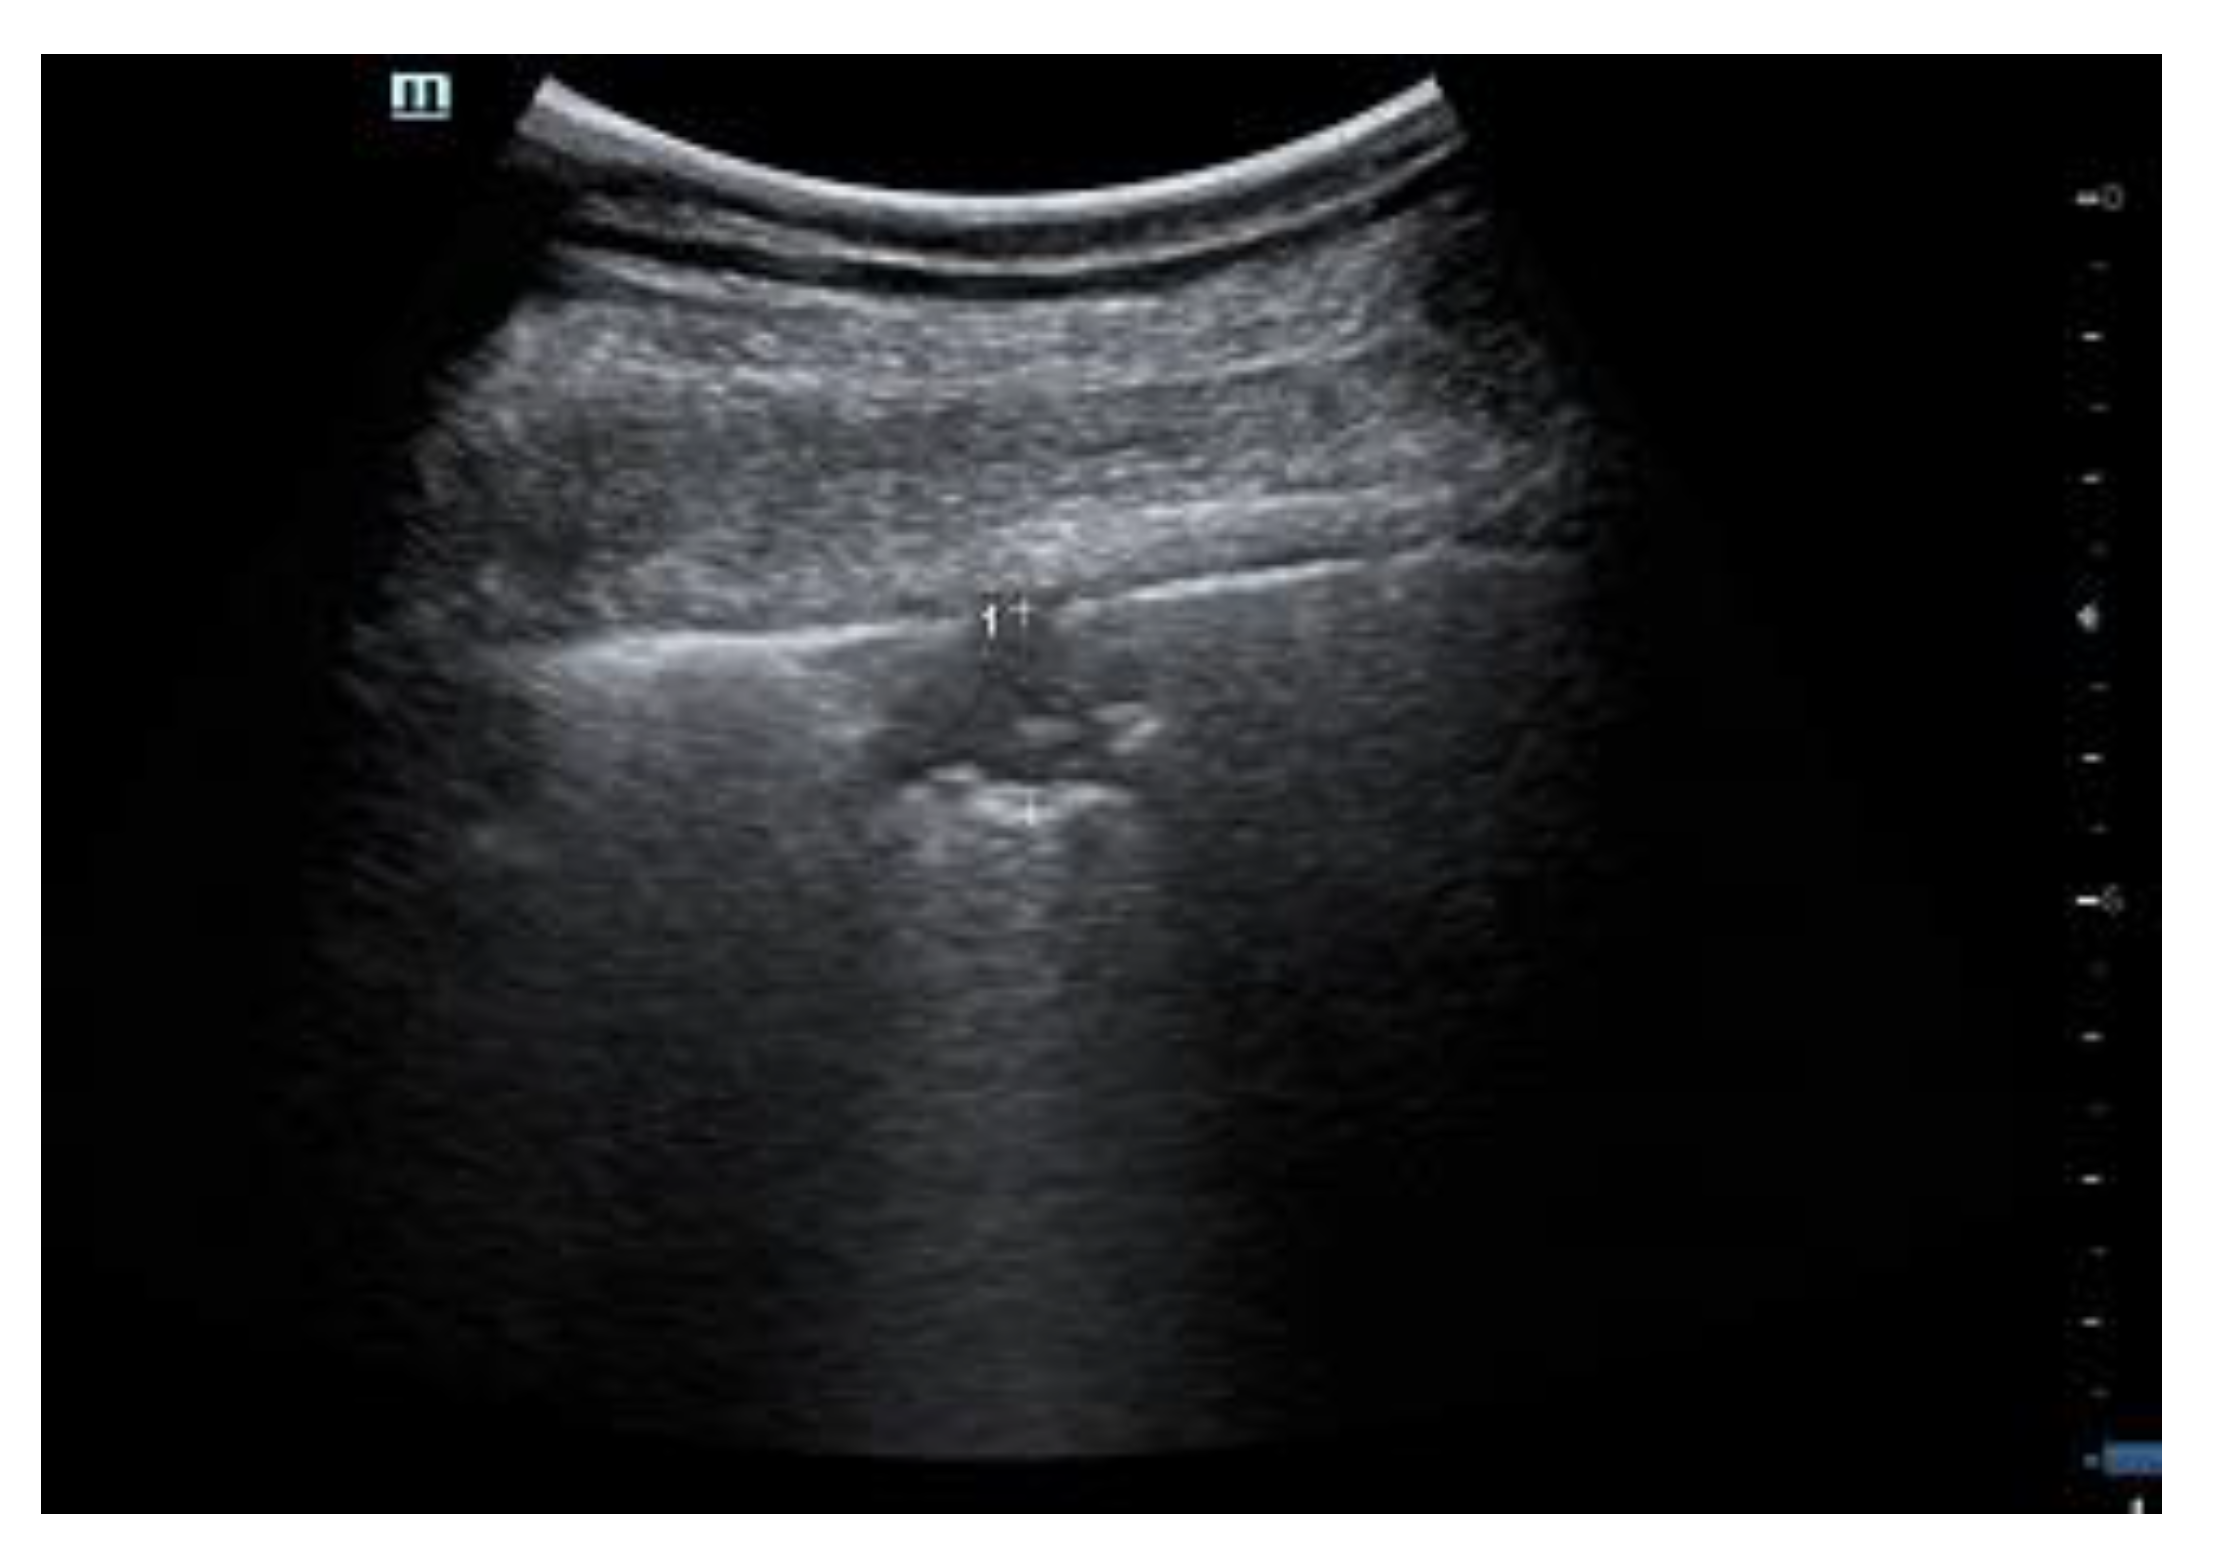

In ultrasound, COVID-19 consolidations have the appearance of small cuneiform lesions abutting the pleura, often containing a central echogenic spot of residual air (Score 3), surrounded by white lung (see Figure 5).

Figure 5. Patient with COVID-19 lung involvement. A small consolidation under the pleura, surrounded by white lung.